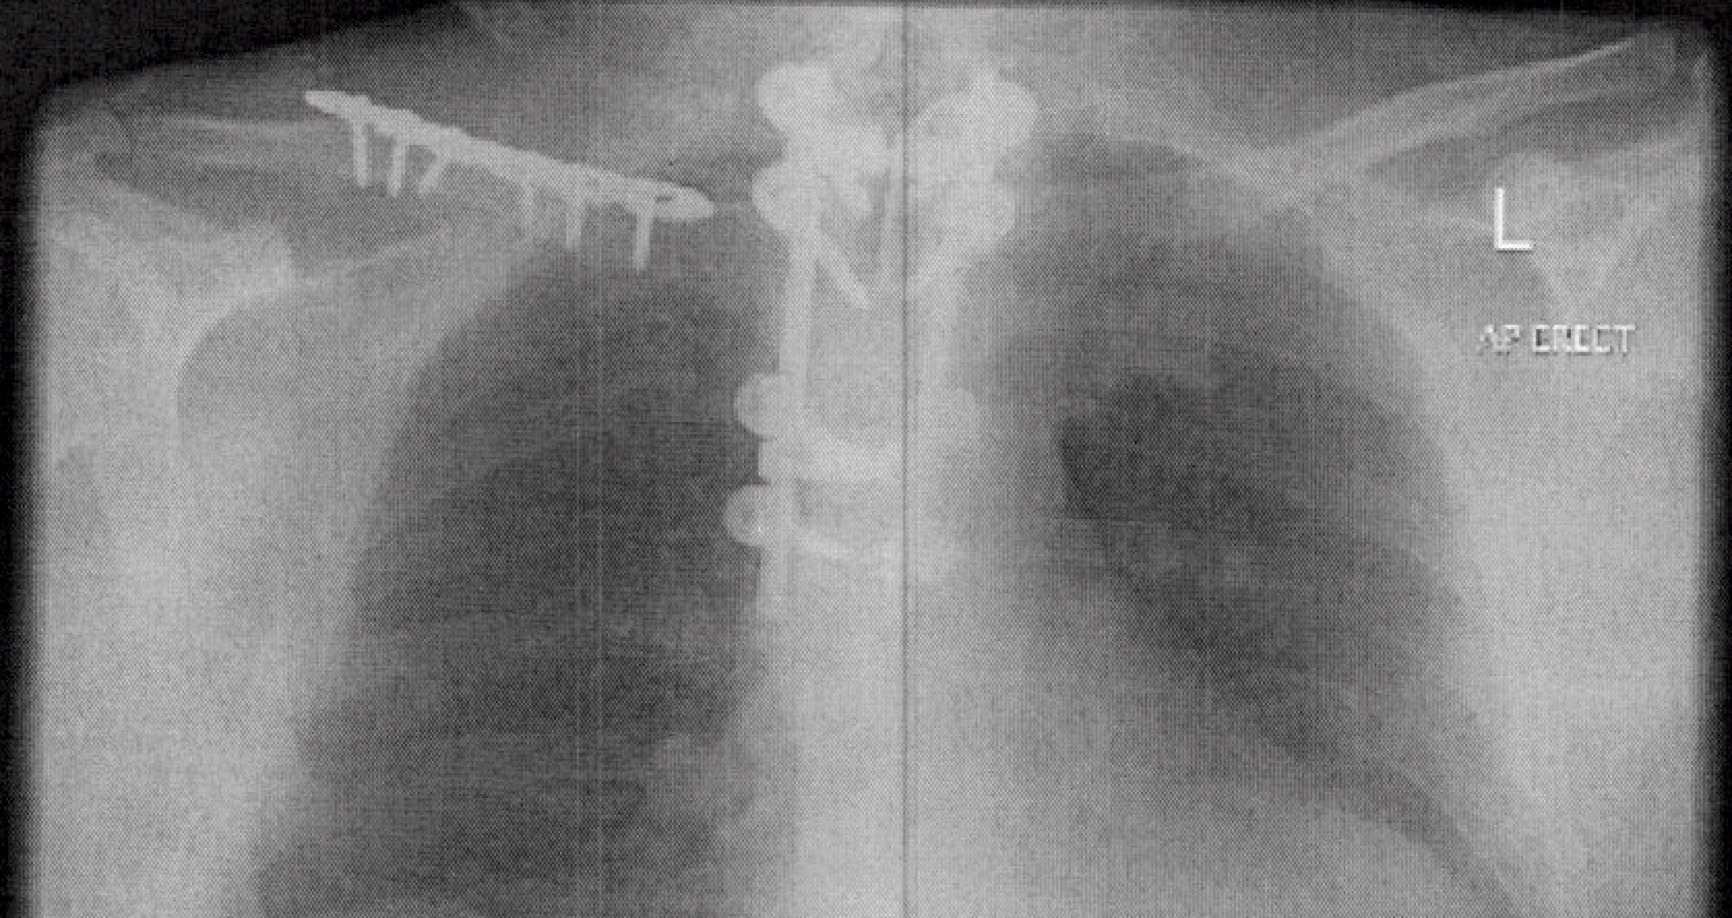

I slept for the majority of each day. Often, I was in pain and required assisted ventilation for weeks due to the injuries to my chest. Pneumonia started developing on the third day, and during my time in ICU, there were regular suctions performed to remove fluid from the lungs. A breathing tube was required for eleven days and finally replaced by a tracheostomy. However, the procedure failed, and CPR was performed for three minutes.

None of the ICU staff would talk about my future, and I assumed there was an unhappy future ahead of me. My leg, ankle and collarbone remained broken three weeks after the accident, as the doctors gave priority to other parts of my body, including the spinal cord injury, heart and lungs.

After 100 questions and multiple examinations by many physicians, the cause of the pain was unknown. Pain levels decreased only slightly after taking a hefty dose of pain relief. I was progressing well through rehabilitation and was due to be discharged soon. The pain has never ceased. It is centred around my level of injury on the sternum and back, as if there is a pole stuck through my body.

The MRI scans indicated I was suffering from Syringomyelia. A cyst (or cavity or syrinx) forms within the spinal cord and grows more significant over time, destroying the spinal cord. It is a serious condition as it may result in pain, paralysis and weakness. There were three separate operations over a few months, and the pain persisted.